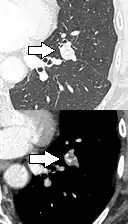

PET-CT of a tuberculoma.